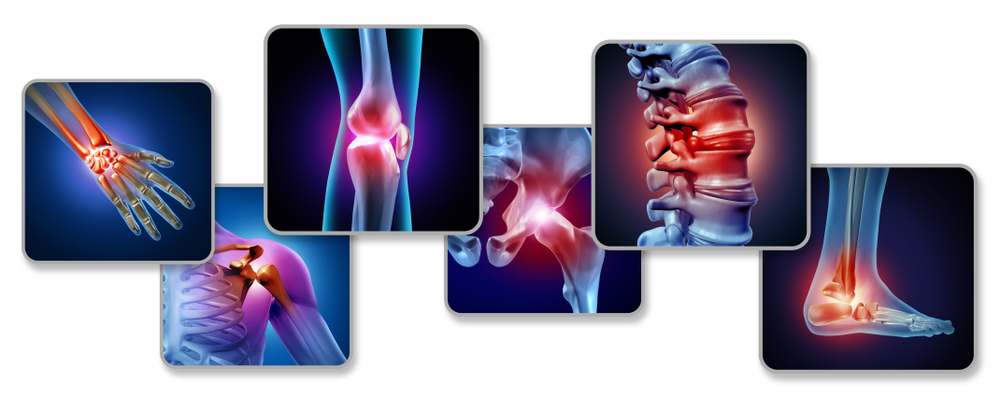

Joint Pain

At all stages of our lives, the necessary nutrients in seafood benefit us in one way or another. The anti-inflammatory effects of seafood can be particularly beneficial to people who suffer from an autoimmune disease. Autoimmune diseases cause the immune system to crash and attack healthy body tissues. Chronic pain from inflammation is a known symptom. Eating seafood frequently can help to manage inflammation and joint pain. It has also been known to ease the symptoms of arthritis.

Studies show that omega-3 may ease tender joints and reduce morning stiffness in patients with rheumatoid arthritis. Researchers credit these benefits to the combination of vitamin D and omega-3 fatty acids, both of which have anti-inflammatory and pain-relieving effects.

Through several studies, these fatty acids have been linked to reducing the pain and inflammation for patients who have lupus, osteoarthritis, rheumatoid arthritis, and inflammatory bowel disease. Though an omega-3 rich diet does not seem to slow the progression of autoimmune disorders, it can reduce your discomfort.